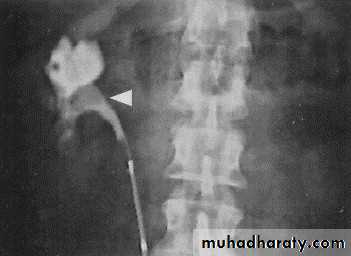

Pyeloxinus reflux may result from rupture of a fornix precipitated by contrast-induced diuresis superimposed on the increased hydrostatic pressure of an obstructed pelvicaliceal system. Urine and contrast extravasate into the renal sinus and perirenal space